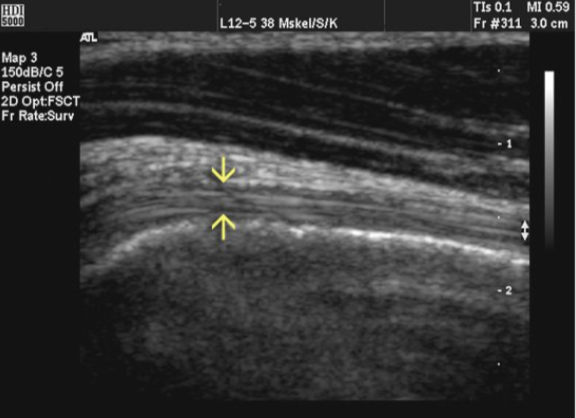

tendons have _______ fibers which are _____ - cord like

collagenous

rounded

when looking at a tendon you should identify echogenic _______ that respresent the _________ fibers to confirm imaging of tendon

fascicles

collagen

the echogenic facicles /collagen fibers run _____ to long axis of tendon

parallel